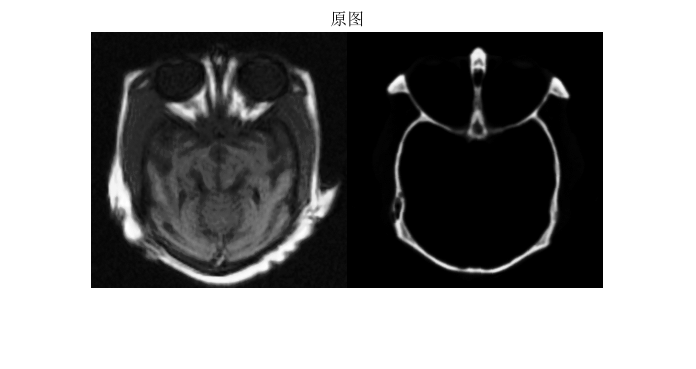

医学图像融合是指将不同模态医学影像(如 MRI、CT、PET)的互补信息整合为单幅图像,以提升临床诊断与治疗规划的准确性。其中,MRI(磁共振成像)与 CT(计算机断层扫描)的融合是临床最常用的组合之一,广泛应用于肿瘤诊断、神经外科手术规划、骨科植入评估等场景:

理想的 MRI-CT 融合需满足信息完整性(保留双方关键特征)、空间一致性(无几何错位)、视觉清晰度(无伪影) 三大核心需求,传统融合方法(如简单加权、金字塔分解)难以平衡多模态图像的特性差异,需借助更精准的图像增强与特征提取模型。

⛳️ 运行结果